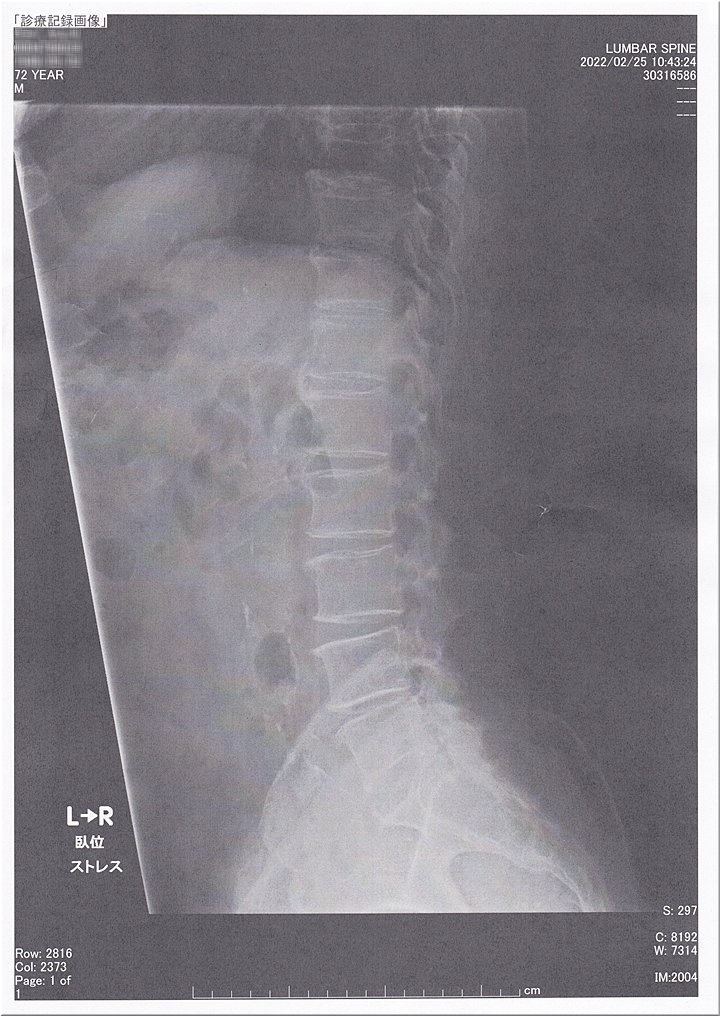

本日は、手術後6ヶ月毎定期検査で、福山医療センター行きのGONsanでした(^.-)☆

昨年の2月末でしたか…腰部脊柱管狭窄症の手術を行いまして、早や1年が来ようとしております。

以降は、6ヶ月毎に定期検査を受診で、本日がその定期検査日で国立病院機構福山医療センター行きのGONsanでありました。一昨年の秋でしたか…突然、右足に激痛を生じ歩けなくなってしまいまして、主治医に診て貰いますと「腰部脊柱管狭窄症」と診断。

で、紹介状を手に、急いで福山医療センターで手術の手配を終えたのは良かったのですけど、不運にも福山医療センターでコロナのクラスター発生。

お陰で、10月--11月--12月--01月…と、手術予定日は変更、変更の繰り返しで、ヤッと手術して貰えましたのが昨年の2月末でありました。

車には乗れますし勤務も可能。日常生活では何ら不自由は無いのですけど、ただ、50m程度以上は激痛で、とても歩けない。こんな苦しい時期が5ヶ月近く…

待望の手術以降は、手術後2日目からは、通常の元気な足にと復帰しまして、痛みも無く病棟内を歩き廻れました時には、もぅ嬉しくて\(^o^)/

それから早や1年ばかり…当時がウソのように感じられてしまいます。

まだ6ヶ月毎の定期検査が続いてはおりますけど、6ヶ月毎に福山医療センターを訪れますと、懐かしさが蘇ってしまいます。

ただ、今回の定期検査では、検査結果を聴きますのが少しばかり怖さも…

…と言いますのも、昨年の12月でしたか…鞆の古道(山田街道)を歩きグリーンラインに抜けます際に、積み重なった落ち葉に足を滑らせ転倒し、尾てい骨を強打。この時には、当分、臀部に痛みが残りましたけど、足には何らの影響も…

ですが、こんな経緯がありますだけに、検査結果を眼にしますまでは、内心、ヒヤヒヤ状態ではありました。

結果は、脊柱管には異常なし。ヤレヤレでしたネ(^_^)v

先生に、転倒し尾てい骨を、しこたま強打した旨を話しますと、痛みが無ければ大丈夫。異常が出れば痛みがあるから…との事でありました。

…と言う事で、次回の定期検査は8月ですネ。

こんな調子で、手術後3年間は6ヶ月毎検査が続いて行きますのでしょうけど、1年前の外来患者sanの少なさとは一転、現在は、福山医療センターsanも、以前の混雑に戻りましたようですネ。

A.M.11:00に予約のGONsanで、10:30に福山医療センターにヤッて来ましたけど、駐車場に入りますまで5台待ちでありました。診察を終え、退散時の正午過ぎには、空きスペースも結構有りましたが(^-^)

ここ近年は、腰部脊柱管狭窄症でお苦しみの方も多いとか…ブロック注射で治癒される方もおられますのでしょうけど、GONsan的には、原因が明確なのですから手術をお勧めしたいですネ。

原因を手術で除去しませんと、完治は望めませんのかも…